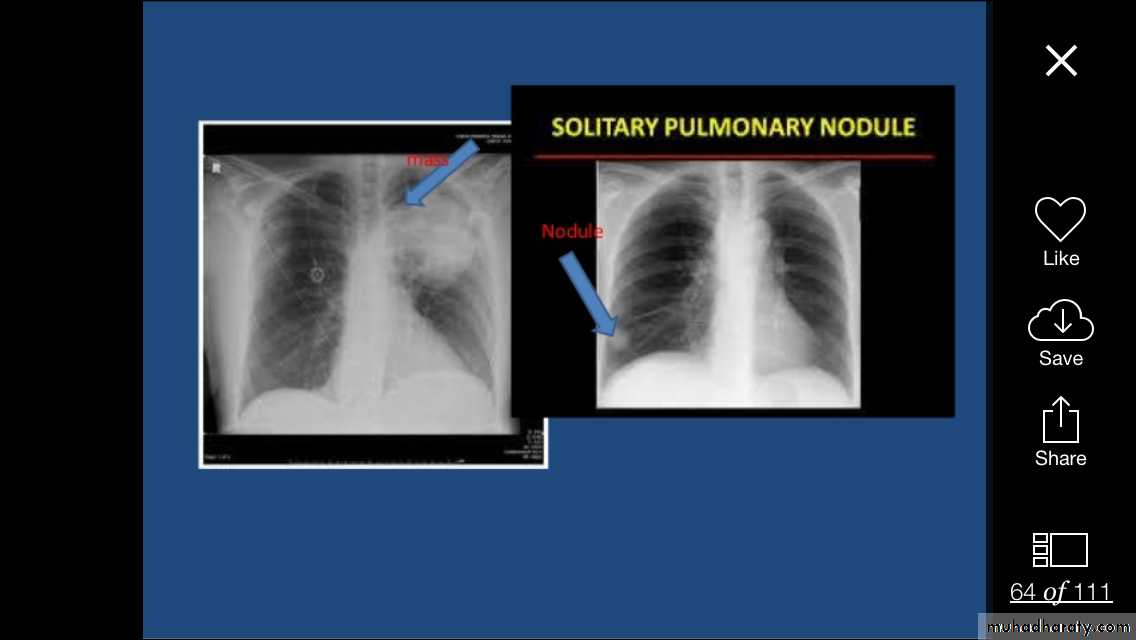

Focal lung diseases-nodule

- mass

Focal ( Solitary or multiple )Diffuse ( alveolar or interstitial )

5mm-20mm=nodule

Pulmonary nodule /s1) Bronchogenic CA ( spiculated )